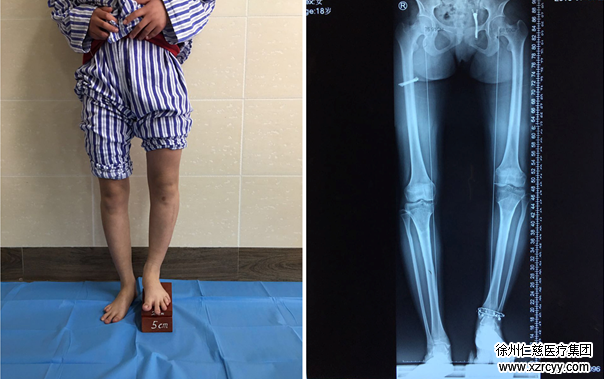

今年18岁的婷婷(化名),在4年前的一次O型腿矫形手术后,肢体短缩伴内翻畸形,到今年2月,左腿竟然比右腿短7厘米。诊断后,betway在线登陆骨科医生团队决定为其应用Ilizarov技术实施肢体延长术。2月7日手术成功进行。

左右腿相差7厘米

2013年,因为天生四肢畸形,婷婷曾在外院接受O型腿矫形手术,术后左下肢较健侧短缩畸形。刚开始,因为差别不明显,家人也没太在意。可随着逐渐长大,父母发现,婷婷两条腿明显不一样长,走起路来,身体往左侧倾斜。为此,婷婷父母带着她四处求医,可都没有找到较好的治疗方案。

接诊的betway在线登陆骨科医生徐明亮检查后发现“双下肢全长X线片显示,左胫腓骨畸形明显。”一测量,婷婷的左下肢较右下肢短7cm。综合考虑后,徐医生给出了治疗建议“应用Ilizarov技术做肢体延长术,能帮助婷婷延长左胫腓骨长度,达到左右腿长度一致的效果。”

(图为双下肢全长X线片)